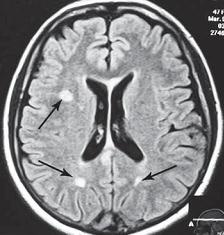

Однако меня не удовлетворили результаты его обследования. Если бы дело было только в грыжах, это полбеды. Меня смущало наличие других симптомов, которые косвенно свидетельствовали о возможном поражении ЦНС. Поэтому я послал его на дополнительные обследования МРТ головного мозга (№ 33), тесты (ИФА (иммуноферментный анализ), ПЦР (Полимеразная Цепная Реакция на инфекции), которые дали положительный результат на герпесвирусы: Epstein-Barr virus (EBV) (вирус Эпштейна-Барр) и Cytomegalovirus (CMV) (вирус Цитомегаловирус).

МРТ № 33

МРТ № 33 На МРТ отчётливо видны множественные очаги демиелинизации, вследствие развития нейроинфекции

Этот случай очередной раз указывает на то, как даже гениальный мозг может пострадать от банальной глупости человеческой. Есть такие замечательные слова древнекитайского философа Лао-Цзюнь (Лао-Цзы) в «Рассуждениях о ста заболеваниях»: «Человек мудрости… избавляется от беды, когда она ещё не появилась. Ведь катастрофа рождается из мелочей, а болезнь возникает из тончайших отклонений».